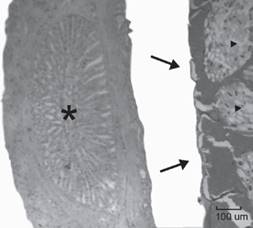

Using light microscopy, the nematodes were identified as spiruroids of the genus Procyrnea (Spiruroidea: Habronematidae) according to the following characteristics: the body presented fine transverse striations, buccal region consisting of two pseudolabia and dorsal and ventral labia each consisted of two submedial lobels and small teeth on the border of pseudolabia, thick-walled buccal cavity, esophagus divided into a short anterior muscular part and a long posterior glandular part, a coiled male tail with caudal alae, unequal spicules, presence of a gubernaculum, and a vulva in females near their midbody (Chabaud, 1975). Two specimens were females measuring 5.82 × 0.40 mm and 7.5 × 0.58 mm (average, 6.66 × 0.49 mm) and one male measured 4.8 × 0.52 mm (Fig. 2). The length of the muscular and glandular esophagus was 320-480 and 1.45-1.7 mm, respectively. The nerve ring was located in the middle of the muscular esophagus and the excretory pore immediately posterior to nerve ring. The tail was curved and ended in a tip point. The male had 2 unequal sized spicules in its tail: the left spicule was bigger (1.45 mm) than the right one (220), the ratio of right spicule-left spicule was 1:6.5, neither was splintered, and both distal ends were blunt (Fig. 3). One uterus had embryonated eggs with oval shape and smooth thick shells that measured 45 μm × 27.5 μm in average (Fig. 4). Analysis of proventricular histological sections indicated that the submucosa contaided parasitic structures which pressed and atrophied the adenomeres adjacent to the parasite (Fig. 5).

This is the first documented case of Procyrnea sp. from a Rupornis magnirostris in Mexico. Most references of this parasites have been published from Europe and a few from the US, Costa Rica, and Brazil (Siegel et al., 2012; Pinto et al., 1996; Zhang et al., 2004). While in the current report the general characteristics of the nematodes and the eggs found in the female uterus are in agreement with those of nematodes from the order Spirurida and the genus Procyrnea (Zhang et al., 2004; Quentin et al., 1983; Vicente et al., 1995), there is no previous publication in which a Procyrnea species is associated with this kind of gross and microscopic proventricular lesions described herein. Most reports have identified this parasite to infect the ventriculus (Pinto et al., 1966; Vicente et al., 1995; Zhang et al., 2004, 2011), but only few cases have mentioned the proventriculus, besides the gizzard, as site of infection (Sanmartín et al., 2004; Salcedo & Villa, 2001) and very few cases have described proventricular lesion associated to Procyrnea (Salcedo & Villa, 2001). In the case described herein, no gross lesions were detected in the gizzard. Furthermore, the characteristics identified in the male parasite found in the present case differ from others previously documented: both spicules had a blunt end, whereas in other cases one or both spicules had sharp or barbed ends. The present study described the presence of adult male and female Procyrnea sp. detected in the proventricular submucosa and serosa of Rupornis magnirostris. The effects of Procyrnea in wild birds have not been clearly elucidated. Salcedo & Villa (2011) observed epithelial destruction in the proventriculus and gizzard in Palawan hillmyna infected with P. graculae. Foster et al., (2002) found macroscopic changes in texture, color and integrity of the cornified epithelium in the gizzard of red-bellied woodpeckers associated with P. pileata infection.